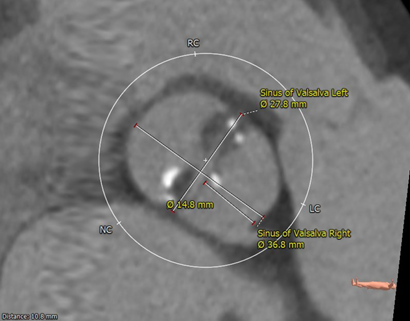

主动脉根部解剖

Type0型二叶瓣,有钙化(HU850:391),延续至LVOT,主动脉瓣瓣环周长71mm,平均周长径22.6mm。

左冠开口高度较低,仅7.6mm,有冠脉堵塞风险;右冠开口15mm,无明显冠脉堵塞风险。